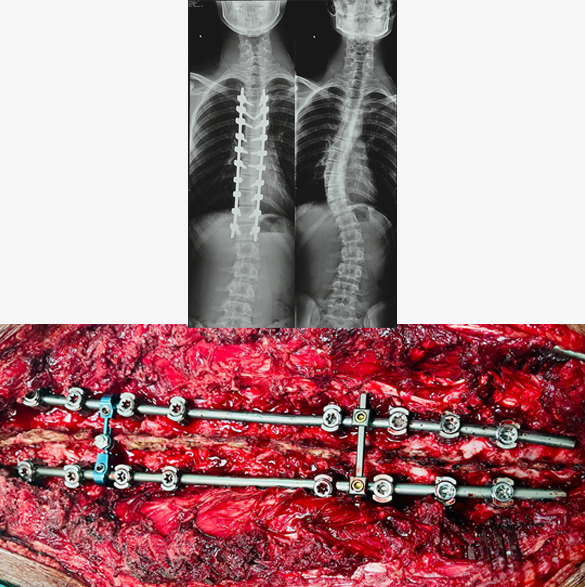

Deformity Surgery for Scoliosis

Scoliosis reconstructive surgery, primarily spinal fusion with instrumentation, aims to correct spinal curvature by fusing vertebrae together and stabilizing the spine with metal rods and screws. This procedure is often recommended for severe scoliosis cases, particularly when the curve exceeds 40 degrees or moderate scoliosis where patient has severe symptoms. Deformity surgery is a type of complex spinal procedure where the surgery time is long and require an extensive investigations prior to surgery. While generally successful, it's a major surgery with potential short-term and long-term effects. Complications of this surgery may include infection, bleeding, weakness or paralysis, and screw/rod misplacement.